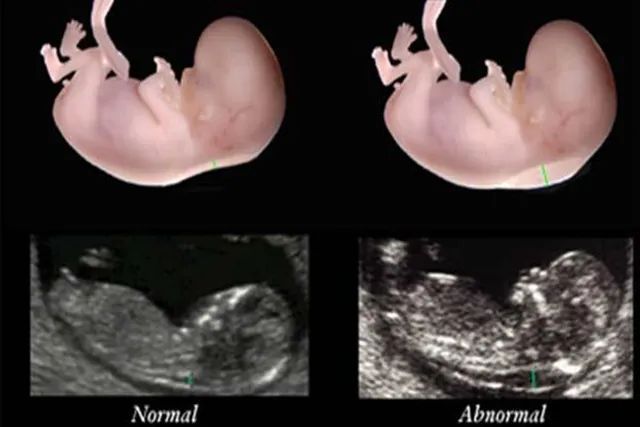

03那么怀孕三个半月的胎儿,发育成什么样了呢?

这时胎儿已经开始出现眼睛、鼻子等器官了,而且就连手指、脚等部位也能清晰的分辨出来。看起来就是一个正常的宝宝,非常可爱。

通常在三个月的时候胎儿已经成型,身子长度可以达到7.5到9cm左右,脊柱也开始形成。

而三个半月的胎儿已经开始会吮手指,或者触碰脐带和自己的手臂了,就连脑部都发育完全了,这时就可以赶紧对宝宝进行胎教了。